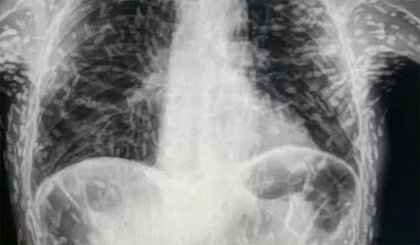

Um exame de radiografia do tórax foi bastante comentado nas redes sociais nos últimos dias. A imagem surpreendeu os internautas, pois o tórax do paciente estava contaminado por larvas.

A radiografia foi publicada no Twitter pelo médico generalista Vitor Borin de Souza, residente no Hospital das Clínicas da Faculdade de Medicina de Botucatu. Segundo o especialista, o exame apresentava um caso de cisticercose disseminada, em que as larvas do verme Taenia solium — também conhecida como solitária — se espalham pelo corpo.

O médico relatou que o paciente tinha tosses constantes há dois meses e solicitou o exame de raio-x.  Apesar da quantidade, o profissional apontou que as lesões por larvas já estavam calcificadas e não representavam riscos ao paciente.

No caso do paciente da radiografia, por exemplo, o tratamento não foi indicado por se tratar de lesões já calcificadas.